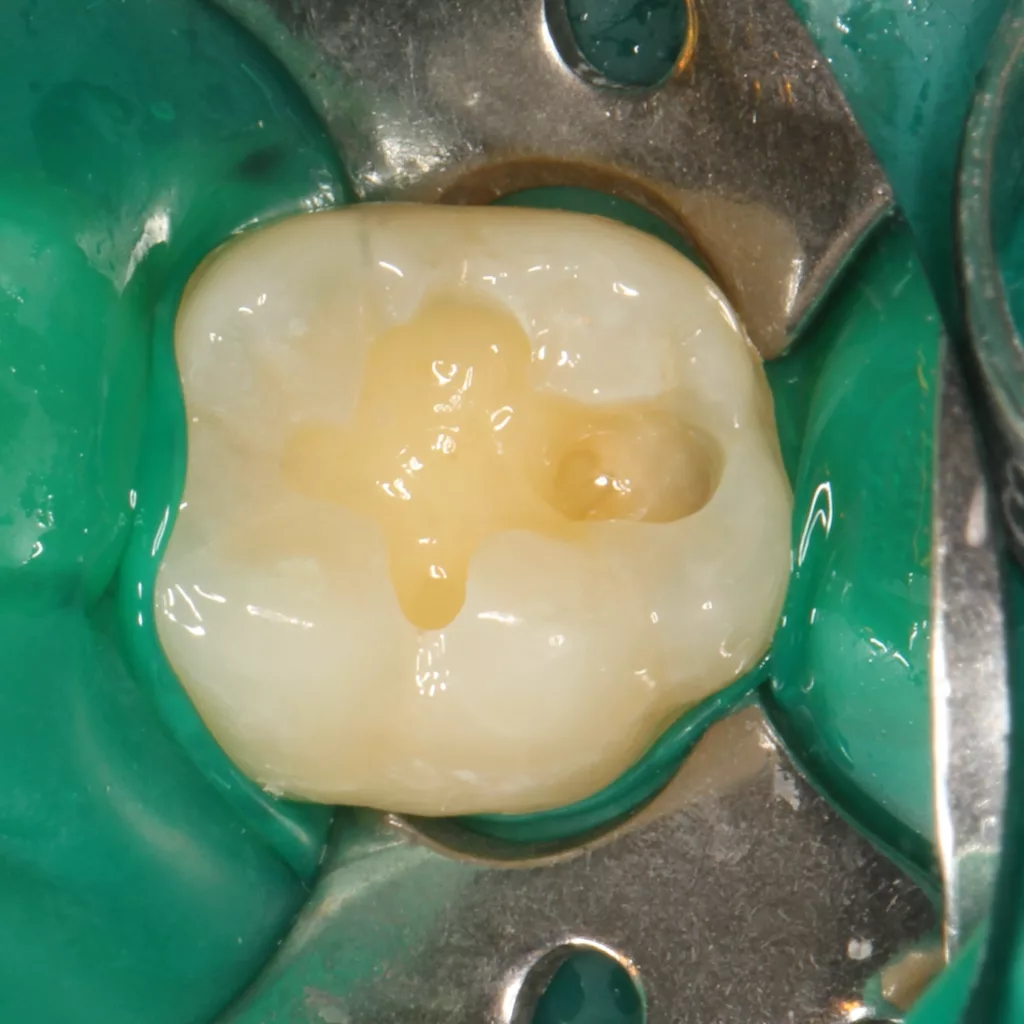

Fall 5: Versorgung einer okklusalen Kavität an einem unteren Molaren

Auch im Molarenbereich können Bulkflow-Materialien effektiv und ökonomisch eingesetzt werden, ohne Abstriche an der Ästhetik machen zu müssen, was der Fall des hier versorgten Zahnes 46 bei einer 22-jährigen Patientin zeigt. Die Abbildung 24 stellt die bereits präparierte und mit einem Einzelzahnkofferdam isolierte Kavität mit der Phosphorsäurekonditionierung der Schmelzränder (Gel Etchant, Kerr) dar. Die Entscheidung zur absoluten Trockenlegung fiel aufgrund der nicht so einfach kontrollierbaren Zunge und der vielen Schluckreflexe, was das Risiko einer ungewollten Speichelkontamination der Klebefläche unverhältnismäßig erhöhte.

Die Verwendung des Kofferdams ist generell eine sehr empfehlenswerte, aber keine zwingende Voraussetzung zur Etablierung einer suffizienten Kontaminationskontrolle [47,96]. Das bisher auch bereits verwendete Zwei-Schritt-Universaladhäsiv G2 Universal wurde hier in der selektiven Schmelzätztechnik angewendet, d.h., das Material arbeitet auf dem Dentin selbstkonditionierend (Abb. 25). Die bislang zu diesem innovativen Mehrflaschen-Universaladhäsiv publizierten Daten zeigen eine beeindruckende Performance, die den Vergleich mit sogenannten Goldstandards [98] wie einem Optibond FL nicht scheuen müssen [13,18,34,58,63,114,119,127,130]. Im nächsten Schritt wurden die einzelnen Höcker mit dem angenehm standfesten Flowable aufgebaut (Abb. 26). Die Abbildung 27 zeigt die komplett versorgte okklusale Kavität, die Abbildung 28 die Situation unmittelbar nach Ausarbeitung und Politur. Erneut beeindruckt die gute Farbadaptation.